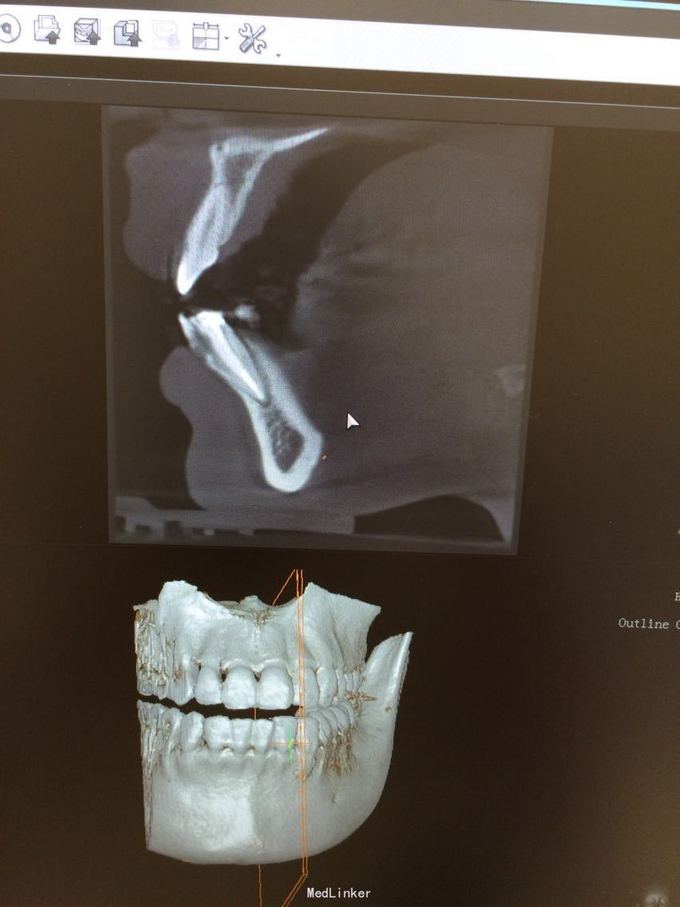

D3完全脱位,伤口血凝块已经凝固,颊侧牙龈钝性撕裂。D2D4无叩痛和松动。脱落牙齿牙体硬组织完好,牙周膜干裂,牙体上有纸屑和食物残渣,根尖有牙髓组织呈黑红色。

D3牙脱位 D3体外根管治疗后垫底充填,盐水和双氧水浸泡后,刮尽牙根的牙周膜后放置盐水和庆大霉素液中15分钟。局麻下刮除牙槽窝内血凝块至流鲜血后盐水和庆大霉素交替冲洗,明胶海绵拭干牙槽窝,浸泡好的牙体植入牙槽窝内并复位,舌侧树脂牙周夹板固定D123456,牙周上派丽奥。随诊